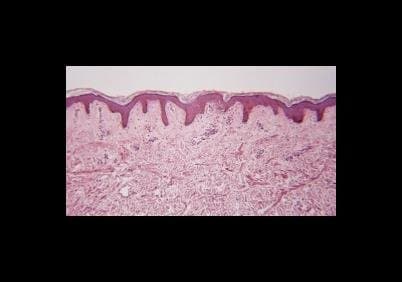

Galleria